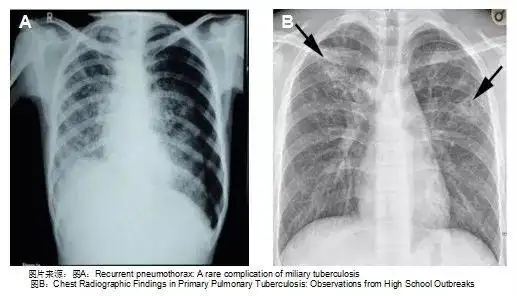

分布平均,密度相似,巨细一致的粟粒状结节(原发性肺结核,哑铃状的原发